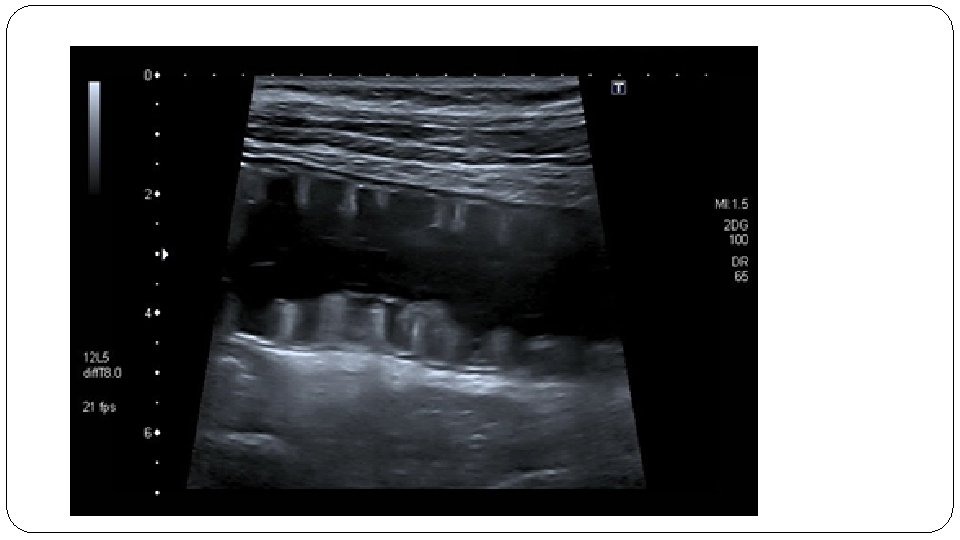

Ultrasound